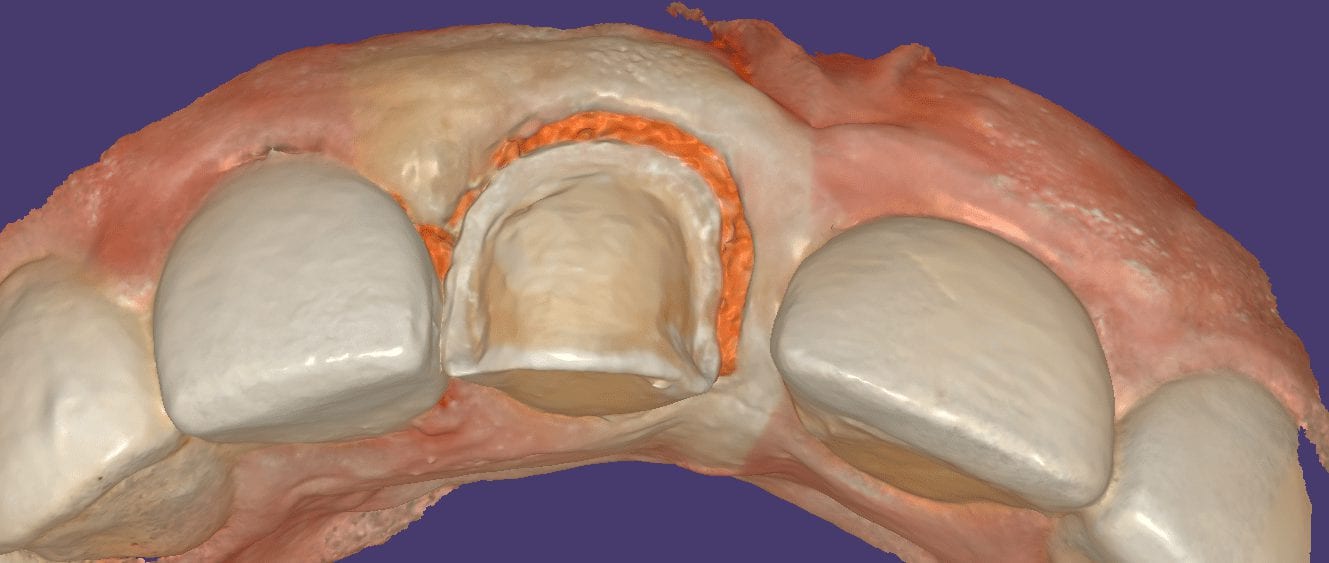

With digital dentistry, you can approach complex cases with ease. For example, when you look at these two crowns that need to be replaced, your inclination is to prep them […]